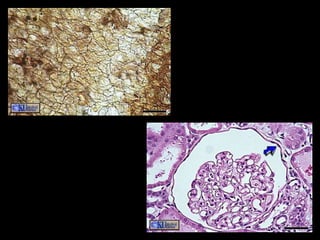

Simple Cuboidal Epithelium

• Structure

– Single layer of cube shaped cells

• Function

– Secretion and transportation in glands, filtration in

kidneys

• Location

– Glands and ducts (pancreas & salivary), kidney

tubules, covers ovaries

Simple Cuboidal Epithelium •Structure – Single layer of cube shaped cells • Function – Secretion and transportation in glands, filtration in kidneys • Location – Glands and ducts (pancreas & salivary), kidney tubules, covers ovaries